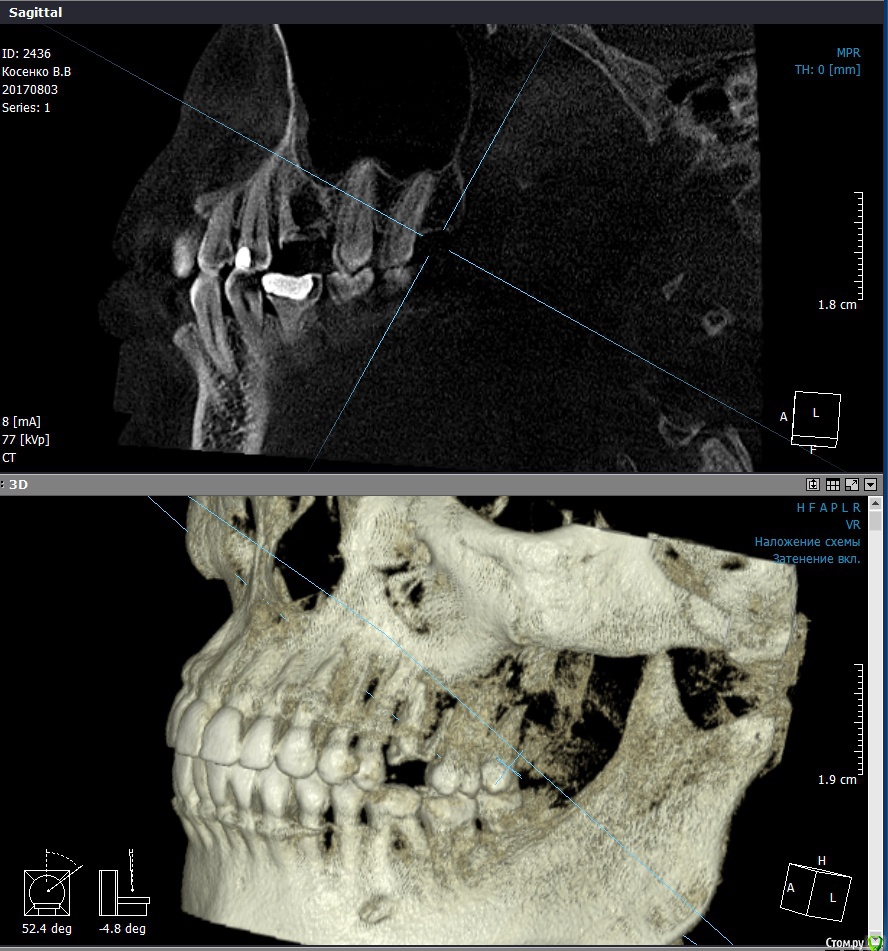

valenkos Опубликовано 20 августа, 2017 Поделиться Опубликовано 20 августа, 2017 Здравствуйте! Уважаемые стоматологи, очень нужен Ваш совет. Над зубом с коронкой появился свищ. Коронку сняла, около месяца ходила без коронки, полоскала водой с солью, свищ не делся. Сделала 3D снимок. Посоветуйте, что делать далее. Вот ссылка на снимок https://fex.net/#!952190258848 Проблемы с верхним угловым зубом с левой стороны. Ссылка на комментарий

valenkos Опубликовано 21 августа, 2017 Автор Поделиться Опубликовано 21 августа, 2017 Сделала скриншоты, пожалуйста, посмотрите Ссылка на комментарий

valenkos Опубликовано 21 августа, 2017 Автор Поделиться Опубликовано 21 августа, 2017 (изменено) Остальные картинки в архиве, так как больше картинок вставить не получаетсяhttps://www.dropbox.com/s/935ee0acbvn775s/Pics.zip?dl=0 Изменено 21 августа, 2017 пользователем valenkos Ссылка на комментарий